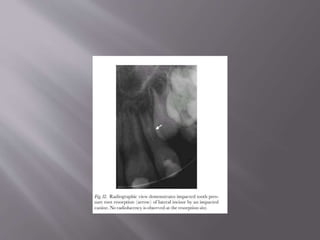

 For impacted teeth or tumors, the resorption

will occur wherever the pressure from the

impaction/tumor occurs

 Usually slow growing lesions- Cysts,

ameloblastoma, fibro osseous lesions and giant

cell tumours.

 Tooth asymptomatic, pulp is vital

 Treatment is relatively easy, in that removal of

the source of the pressure will result in the

cessation of resorption in the majority of cases